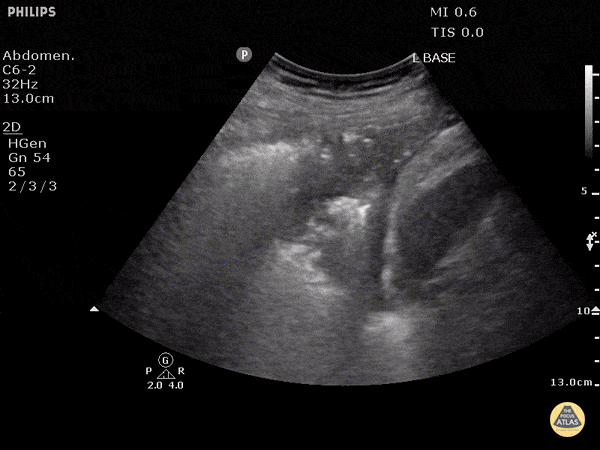

A 34-year-old man with alcohol use disorder presents with fever, profound hypotension, and severe respiratory distress. He is intubated in the ED and started on vasopressors and broad-spectrum antibiotics. Vitals: T 39.4°C, HR 138, BP 74/42, RR 34 before intubation, SpO₂ 82% on non-rebreather. Exam: toxic-appearing, cool extremities, markedly decreased air entry at the left base, coarse crackles over the left hemithorax. Blood cultures later grow MRSA, and CT chest shows left greater than right pleural effusions with left lung consolidation. A left lung ultrasound clip is shown. What are the ultrasound findings, and what is the most likely diagnosis?

What is complex loculated pleural effusion?

What is septic shock due to empyema?